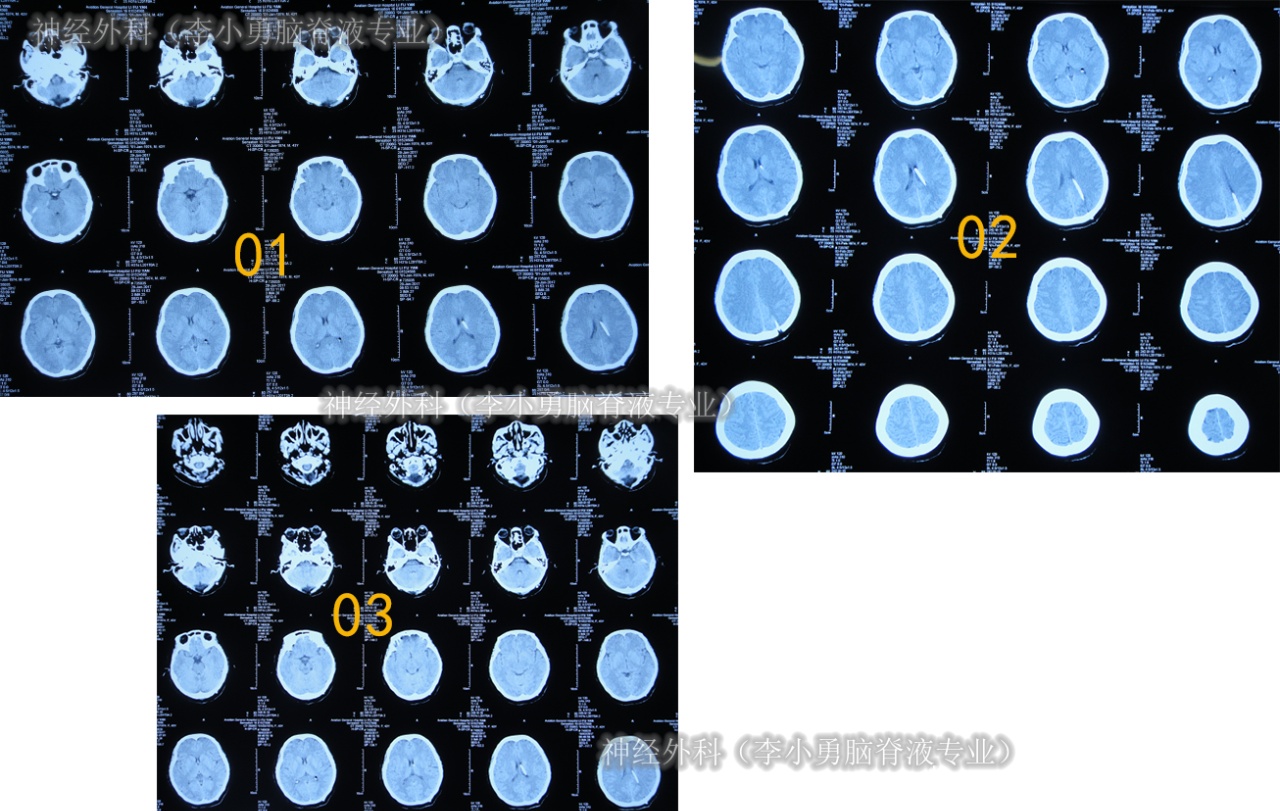

2017年1月9日(后颅窝减压术枕大池成形术62天,发热伴头痛近2月,腰大池引流术后18天,枕部皮下积液9日)住入李小勇脑脊液专业,入院时:间断高热,剧烈头痛,后颅窝疼痛更重,携带外院腰大池引流管,引流管壁内有脓性脑脊液,引流出的脑脊液浑浊;后颅窝术后有积液(图-10)。

图-10:2017年1月9日入院时

入院时查头颅CT示后枕部颅骨缺损,头皮膨出,皮下有积液,触之波动感(图-11)。

图-11:2017年1月10日头颅CT

入院后3天即2017年1月12日,拔除了原外院腰大池引流管+脑室腹壁外引流术(图-12)。

图-12:2017年1月12日头颅CT

住院后7天即2017年1月16日,头痛减轻,引流出的脓性脑脊液消失(图-13)。

图-13:2017年1月16日

2017年3月7日(李小勇脑脊液专业住院57天)出院,出院时:头痛基本消失,体温变正常,皮下积液完全消失(图-15)。

图-15:2017年3月7日出院时